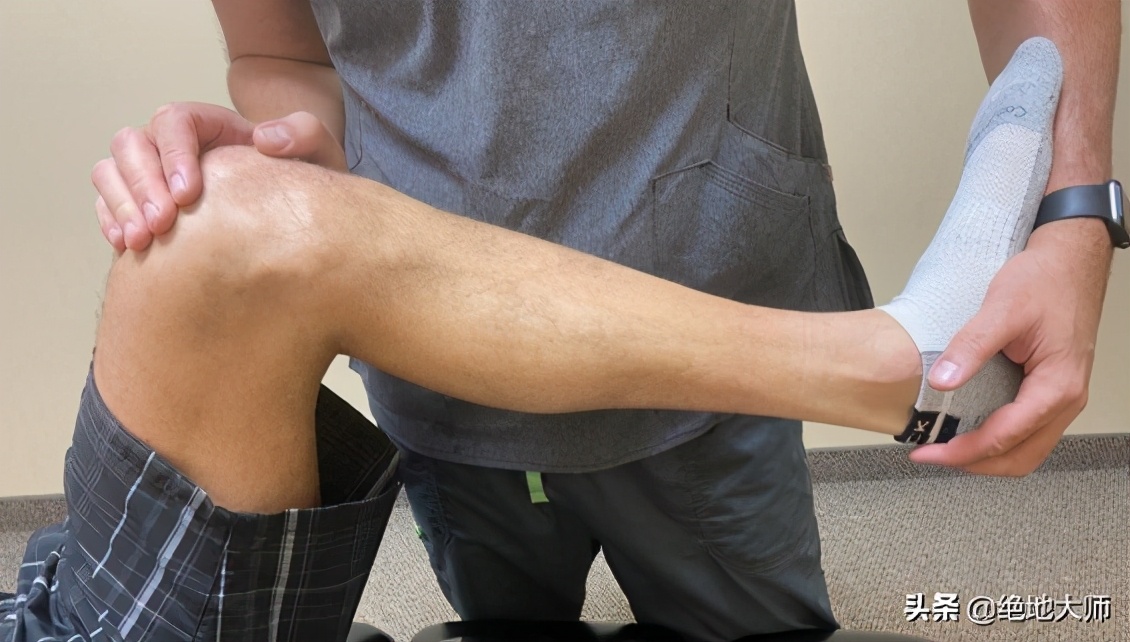

21. ACL LIGAMENT TEST ACL韧带试验

LACHMANS TEST LACHMANS试验:

LIFT LEG OFF OF THE TABLE AT ABOUT 30 DEGREES 抬腿离床约30°(容易)

STABILIZE THE FEMUR WITH ONE HAND 用一手稳定股骨

WITH THE OTHER, TRANSLATE THE TIBIA ANTERIOR AND POSTERIOR

用另一手向前和向后平移胫骨

ASSESS BOTH SIDES AND COMPARE TRANSLATORY MOVEMENT

评估双侧并比较平移运动

(膝关节疼痛评估(2)-ACL韧带试验LACHMANS)